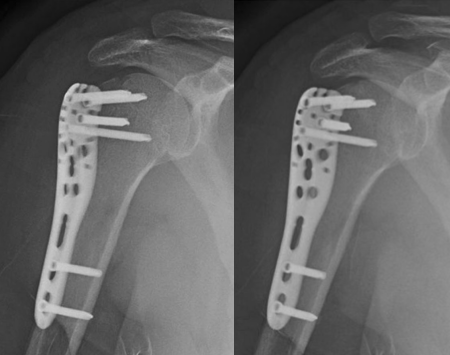

肱骨大结节骨折 ORIF,术前 X 线片显示肱骨大结节骨折情况;术中暴露肱

肱骨大结节骨折 ORIF,术前 X 线片显示肱骨大结节骨折情况;术中暴露肱